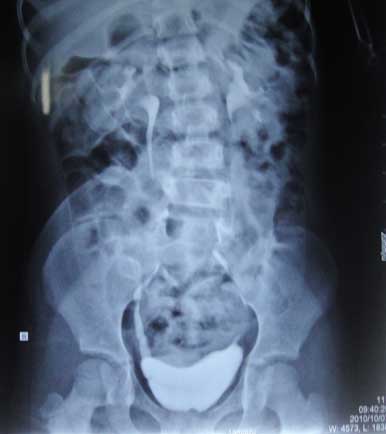

* UIV: chức năng thận còn tốt, không có tắc nghẽn đường bài niệu, bàng quang không teo nhỏ.

*CT scanner:

Hình ảnh CT cho thấy thương tổn đốt sống

Sẹo xấu vùng hạ vị

- Cột sống từ L4 trở xuống cùng cụt hở gai sau kèm theo khiếm khuyết mảnh bên (P) nhiều hơn bên (T).

- Khối phì đại mô với tỷ trọng mỡ trong khoang ngoài màng cứng ống sống đoạn hở gai ( từ bờ dưới L3) phát triển liên tục với mô dưới da vùng cùng cụt.

- Nón tủy vị trí thấp tương ứng L3-L4. Dây tận cùng dày và ngắn, dính ra sau với khối mỡ qua chổ hở gai của S1.

- Thận 2 bên: kích thước, cấu trúc và ngấm thuốc bình thường, niệu quản 2 bên không giãn.

- Bàng quang thành dày lan tỏa, chưa thấy hình ảnh giả túi thừa ( dò qua đường dẫn lưu bàng quang trước đây).

* Kiểm tra bàng quang cho thấy áp lực bàng quang không cao, dung tích bàng quang bình thường, thể tích cặn bàng quang #100ml.

UIV: Trào ngược bàng quang niệu quản P